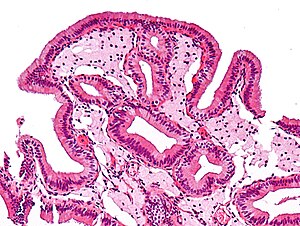

Micrograph of cholesterolosis of the gallbladder, a very common gallbladder disease. Cholecystectomy specimen. H&E stain.